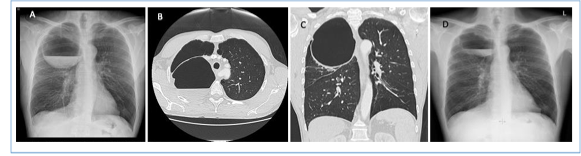

🫁 Publicado en la Revista de Patología Respiratoria “Bulla pulmonar gigante sobreinfectada: evolución favorable con antibioterapia” RPR 2025;28(3):178-179 👏 ¡Enhorabuena a nuestra residente María Conejero por este excelente trabajo! 🔗 doi.org/10.24875/RPR.2… #bulla

🫁 Publicado en la Revista de Patología Respiratoria

“Bulla pulmonar gigante sobreinfectada: evolución favorable con antibioterapia” RPR 2025;28(3):178-179

👏 ¡Enhorabuena a nuestra residente María Conejero por este excelente trabajo!

🔗 doi.org/10.24875/RPR.2…

#bulla